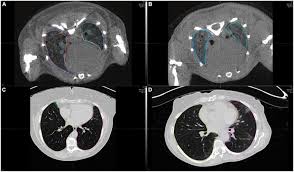

Akciğer hastalıkları, özellikle de akciğer kanseri, dünyada en sık görülen ve en fazla ölüme neden olan hastalıklar arasında yer alır. Bu nedenle erken tanı, tedavi başarısını doğrudan etkileyen en önemli faktördür.

Ancak birçok hasta, hastalık ilerleyene kadar belirti göstermediği için geç tanı alır.

İşte tam bu noktada “düşük doz akciğer tomografisi…